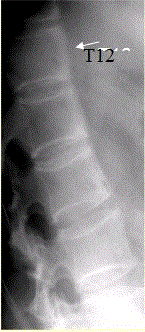

问题 患者男,35岁,外伤后行腰椎CR检查,结果如下图。 观察所给出的MRI图像(下图),你的判断为

选项 A.椎体边缘多发T1WI、T2WI高信号影,考虑为椎间盘退变所致椎体终板改变II型 B.椎体前部上下缘的韧带下骨炎 C.L1~2、L3~4椎间盘信号异常,考虑为椎体结核 D.L1~2、L3~4椎间盘信号异常,考虑为椎体化脓性炎症 E.腰椎退行性改变 F.类风湿性关节炎累及椎体 G.强直性脊柱炎

答案 BG